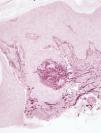

HistopathologyAnalysis of a skin biopsy specimen from the edge of a plaque revealed an acanthotic epidermis with hyperkeratosis, without the presence of intraepidermal neutrophils. Transepidermal elimination of dermal basophilic material was also observed (Fig. 2); orcein staining revealed that the material consisted of elastic fibers (Fig. 3).

Histologic examination of the lesions shows hyperkeratosis with or without parakeratosis, as well as the characteristic transepidermal elimination of material that can be identified by orcein staining as elastic fibers.